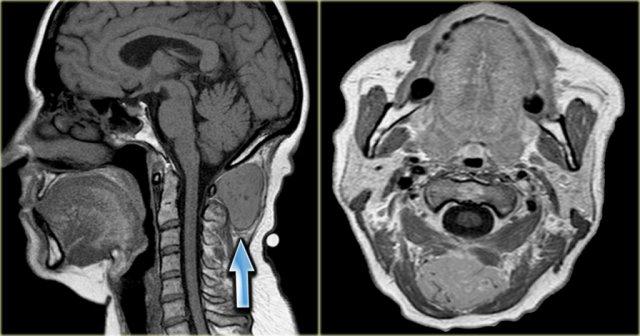

U lympho (2)

Bên trái là hình ảnh của một phụ nữ 67 tuổi có tiền sử u lympho không Hodgkin.

Bệnh nhân gần đây phát hiện sưng nề ở bên trái cổ.

Bước 1

Hình ảnh CT tại mức dây thanh âm thật cho thấy một khối rõ ràng nằm trong khoang cổ sau.

Bước 2

Khối có bờ rõ và đồng tỷ trọng với cơ.

Hình ảnh tái tạo mặt phẳng coronal cho thấy khối có hình dạng thuôn dài, kéo dài về phía nách theo đường đi của đám rối thần kinh cổ-cánh tay.

Tiếp tục xem các hình ảnh MRI.

Tổn thương xuất phát từ lỗ liên hợp thần kinh bên trái và phát triển dọc theo đường đi của đám rối thần kinh cánh tay (mũi tên đỏ).

Thực chất, chúng ta đang quan sát thấy hình ảnh đám rối thần kinh bị dày lên rõ rệt.

Bước 3

Đặc điểm hình ảnh học xác nhận nguồn gốc thần kinh của khối.

Kết hợp với tiền sử bệnh, chẩn đoán cuối cùng là thâm nhiễm lan tỏa đám rối thần kinh cánh tay trái do u lympho không Hodgkin tái phát.